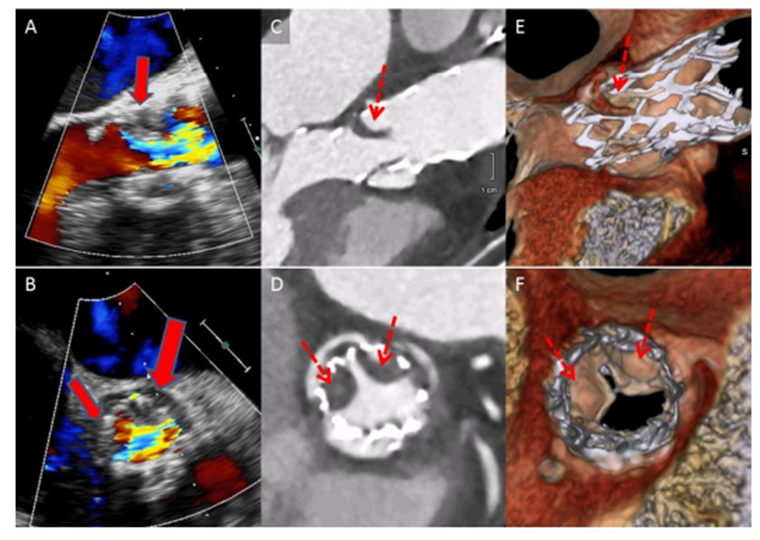

Figura 2 :

Ecocardiograma transesofágico que muestra movimiento reducido de la valva (flecha sólida) en las vistas de eje largo (A) y eje corto (B). Vistas correspondientes de la TC en 2D del eje largo y eje corto que muestran valva con lesiones hipodensas (flecha discontinua). (E-F Vistas correspondientes de tomografía computarizada (TC) renderizadas en volumen del eje largo y eje corto que muestran movimiento reducido de la valva en sístole (flecha discontinua).Modificada de : Makkar, Raj R., Gregory Fontana, Hasan Jilaihawi, Tarun Chakravarty, Klaus F. Kofoed, Ole De Backer, Federico M. Asch, et al. 2015. “Possible Subclinical Leaflet Thrombosis in Bioprosthetic Aortic Valves.” The New England Journal of Medicine 373 (21): 2015–24